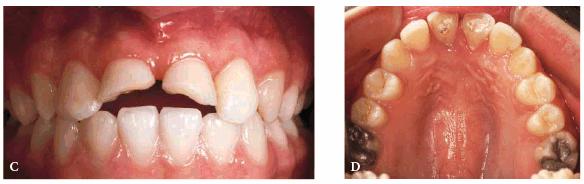

fracture the bonding, then porcelain would be a better alternative (Figur 323s1823d es 18-3A 18-3B 18-3C 18-3D 18-3E and F). In the event that the enamel is

for an indefinite period of time (Figur 323s1823d es 18-4A

and B 18-4C 18-4D and E, and 18-4F

Figur 323s1823d e 18-4A and B: This 17-year-old student fractured her central incisors on the edge of a swimming pool.

Figur 323s1823d e 18-4C: A long bevel is placed using an extra coarse diamond.

Figur 323s1823d e 18-4D and E: The central incisors are bonded with composite resin.

Figur 323s1823d e 18-4F: Five years later, the patient has continued to be maintained with composite resin restorations.